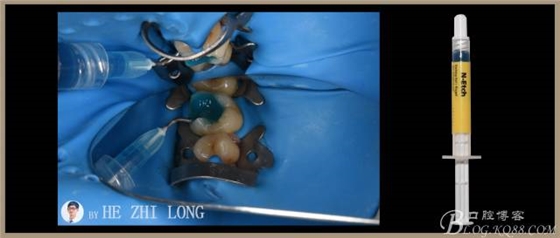

處理:#26去暫封物及腐質(zhì),3Mz350XT流動(dòng)樹脂封閉髓底,3Mz350XT樹脂墊底,制備嵌體洞型,硅橡膠取模,比色3M3,設(shè)計(jì)e.mex鑄瓷嵌體。聚羧酸鋅暫封窩洞。

處理:#26去暫封物,超聲清潔基牙。試戴e.mex鑄瓷嵌體(以下簡(jiǎn)稱瓷嵌體),就位良好、邊緣密合。

下面是使用義獲嘉偉瓦登特Variolink®N粘結(jié)劑粘結(jié)瓷嵌體的具體細(xì)節(jié):

1、橡皮障隔濕,基牙粘結(jié)面噴砂處理或使用不含氟拋光膏清潔。

2、在根管治療和粘結(jié)修復(fù)方面,橡皮障的應(yīng)用為方便牙體手術(shù)操作和確保手術(shù)質(zhì)量做出了重要貢獻(xiàn)。針對(duì)此病例,我想強(qiáng)調(diào)的是,橡皮障夾的喙部與牙頸部應(yīng)有4點(diǎn)接觸,以確保固位穩(wěn)定。此病例在上橡皮障過(guò)程中,由于#25橡皮障夾選擇過(guò)大,與牙頸部?jī)H有2點(diǎn)接觸,導(dǎo)致橡皮障夾的喙部往頸部下滑,壓迫牙齦,給患者帶來(lái)了不適感。